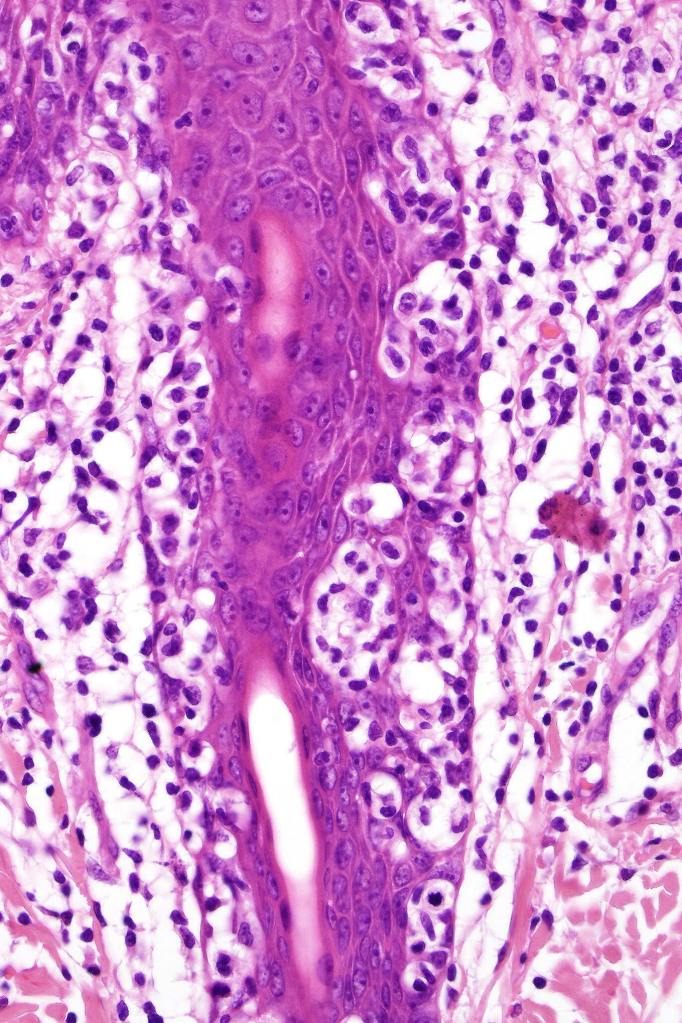

Histological features

•Very marked epidermotropic infiltrate of atypical lymphocytes including Sézary cells

•Perinuclear halo often present

•Pautrier-like microabscesses

•Variable mitotic activity